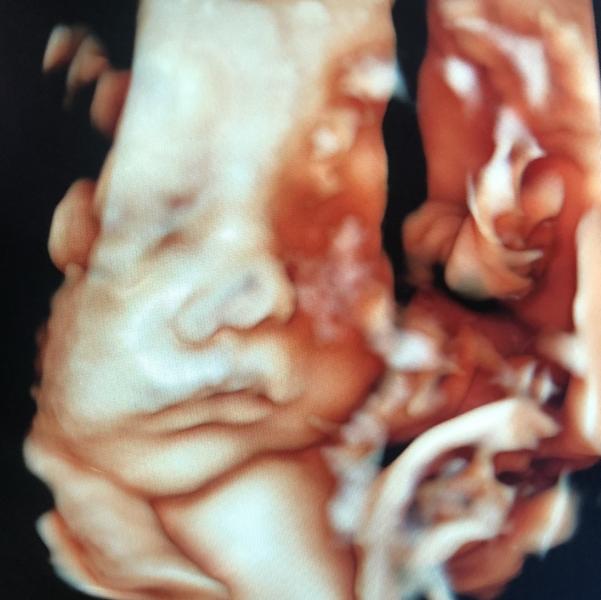

Обалдеть какая точная фотография 😀 уже наверно видите на кого похож!

пока на всех понемножку похож как говорят самые близкие

Но мне кажется что на меня ☺️

У такого человека с красивым носиком точно будет все хорошо))